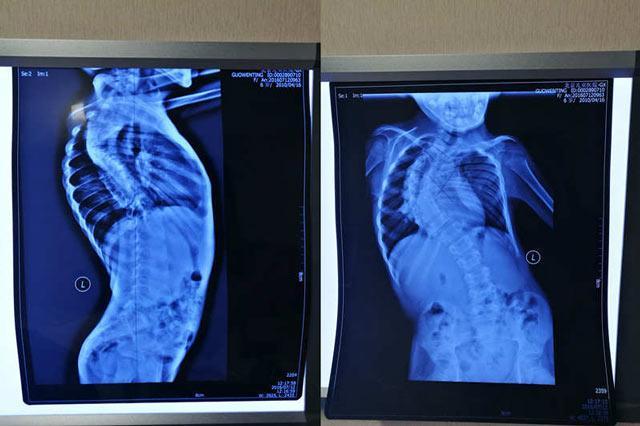

婷婷自幼患有先天性全省股骨头挛缩症并发脊柱侧弯,急需20万元治疗。

- 由于婷婷股骨头挛缩以及严重变形的脊柱,不能正常的行走,大多的时候都是走哪里妈妈抱到哪里。七年来妈妈对她寸步不离,虽然还有姐姐和弟弟,妈妈所有的精力都在婷婷身上。